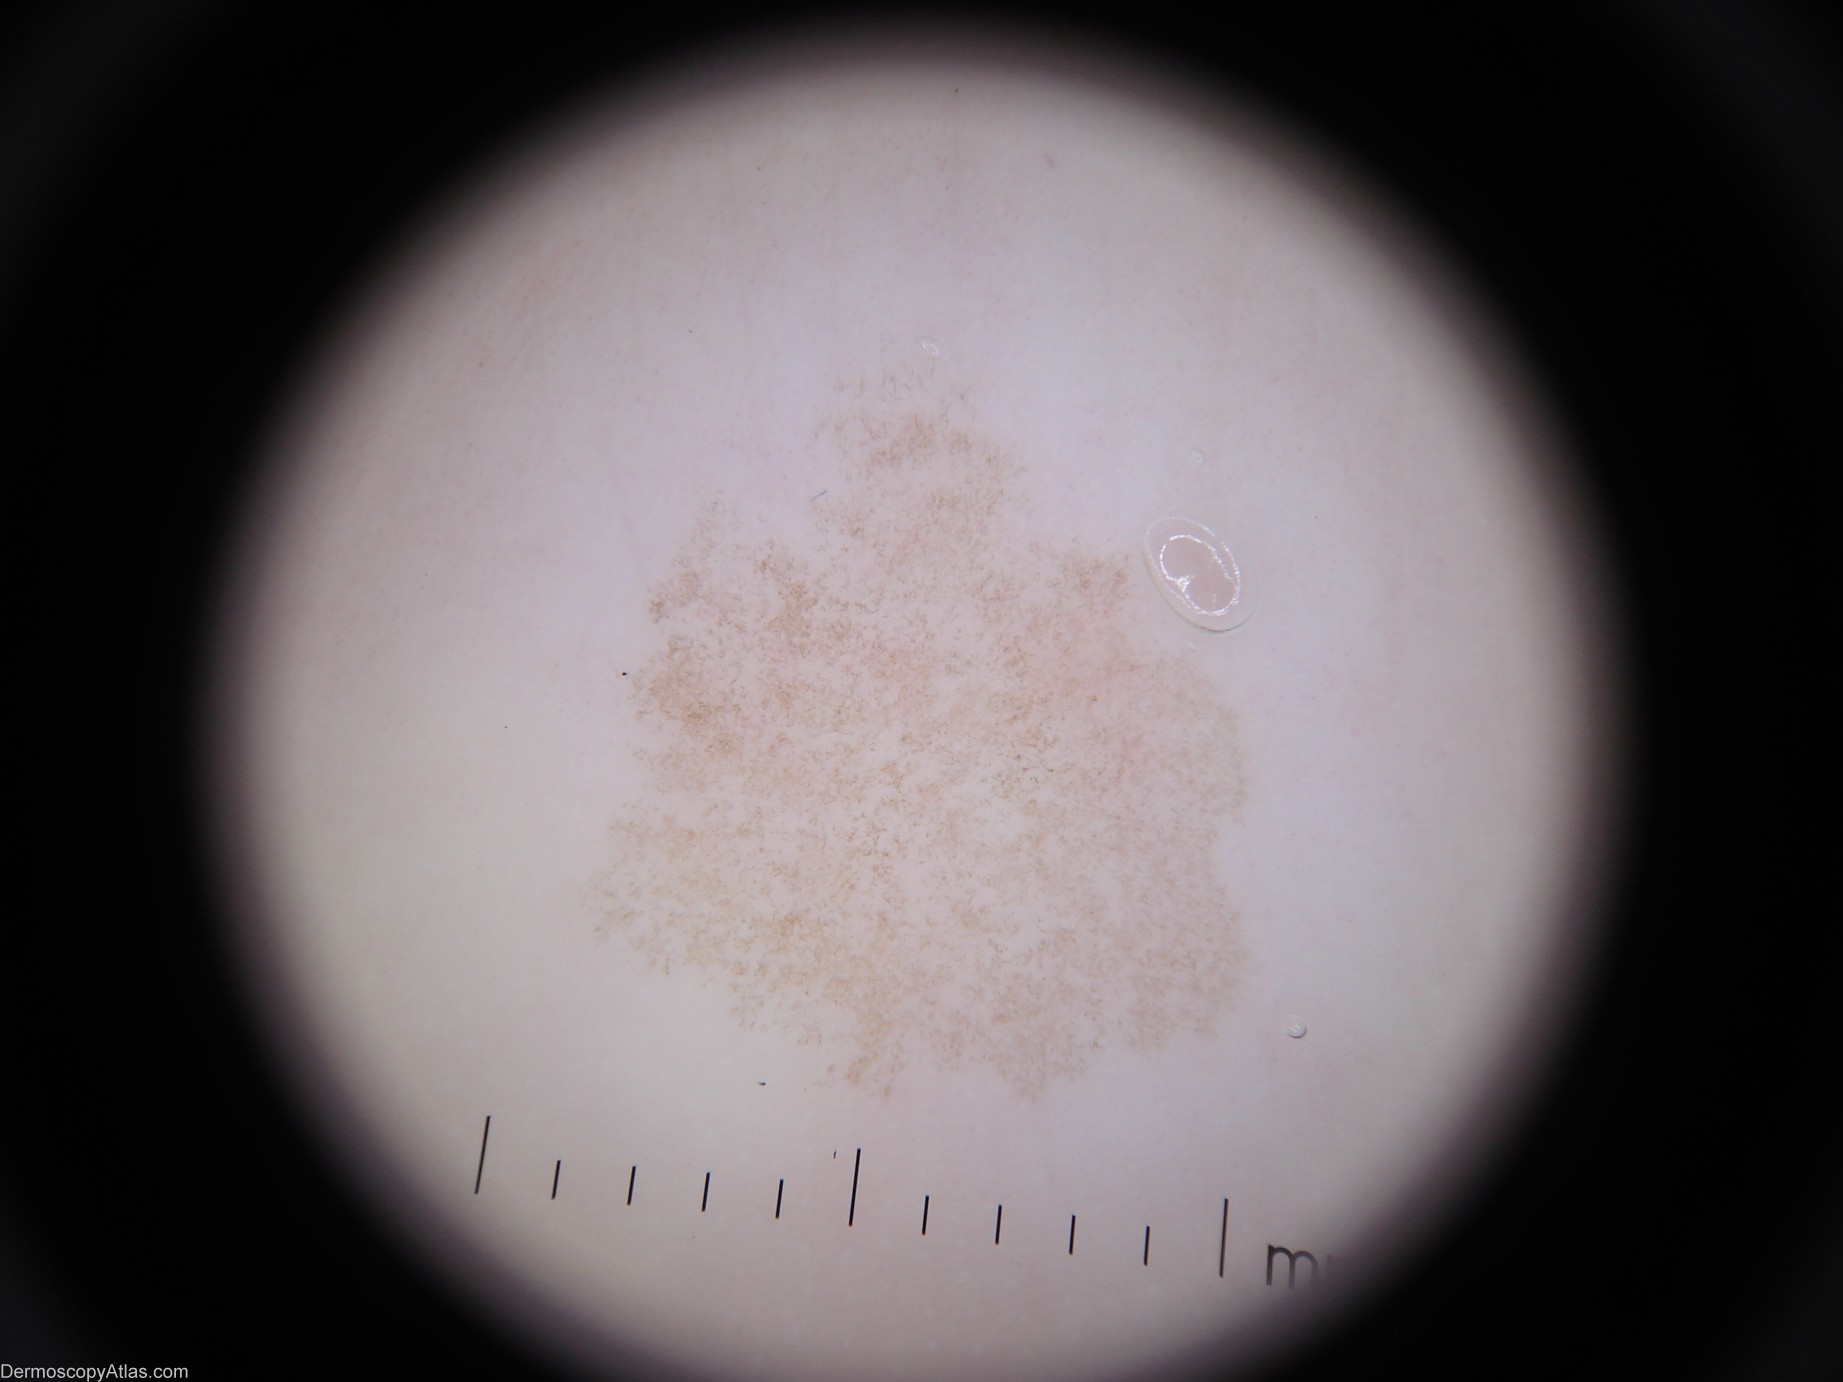

Site: Foot,dorsum

Diagnosis: Tinea nigra

Description: Dermoscopy - There is one colour. Pigment pattern is symmetrical. The pigment appearance is "soft" like a thin veneer of frost on glass. There is no reticular network. The Pseudo-network present is produced by branching hyphae in the stratum corneum of the epidermis. It has neither lines-reticular nor lines-curved. The adjective I would use is "crystalline".

This 42 year old lady with a past history of melanoma presented for a routine skin check and this lesion was encountered

This condition is caused by Exophiala werneckii. It is most commonly found on the palms or palmar surfaces of the fingers and less commonly the plantar or lateral surfaces of the feet. ( Ref Skin Pathology - Weedon 2nd edition page 674)